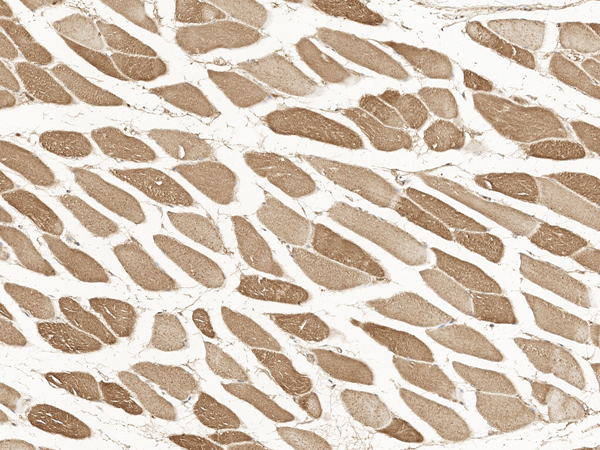

IHC (Immunohiostchemistry)

(Immunochemical staining of human CACNA2D1 in human muscle with rabbit polyclonal antibody at 1:100 dilution, formalin-fixed paraffin embedded sections.)